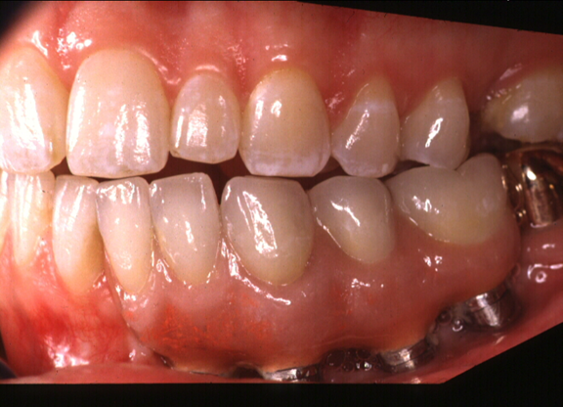

(3.) Prosthesis without access to the intaglio interface.

Figure 3

(4.) Intagilo inflammation of the soft tissue following removal of the prosthesis.

Figure 4

(5.) Prosthesis intaglio surface.

Figure 5

Several factors increasing the risk of peri-implantitis have been reported. Lack of access to the intaglio surface of the implant-supported prosthetics and poor oral hygiene of the implant is reported to increase the risk of peri-implantitis (Figure 3 through Figure 5). Concave intaglio design prevents oral hygiene access (Figure 6). Monje reported that 77.2% of the peri-implantitis cases had inadequate access for cleansability. 9 Serino and Ström found that 74% of the implants had no access to proper plaque control and highlighted the role of prosthesis design.10 Katafuchi suggested that a shallow emergence angle (EA) with a straight or concave transmucosal profile at the interproximal sites should be considered to minimize peri-implantitis risk for bone-level implant.11